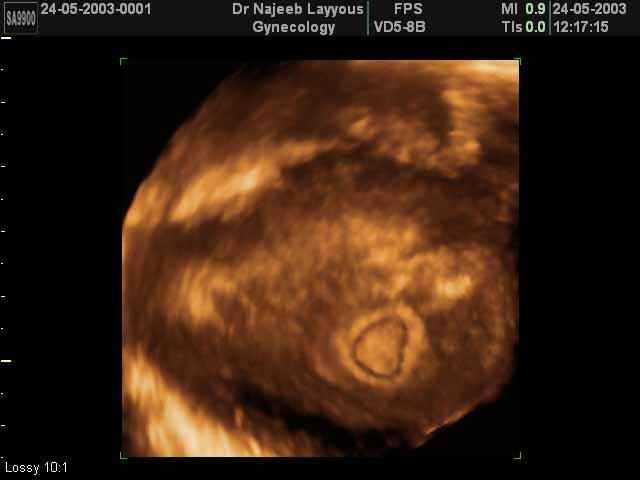

3D First Trimester Ultrasound Scan Photos